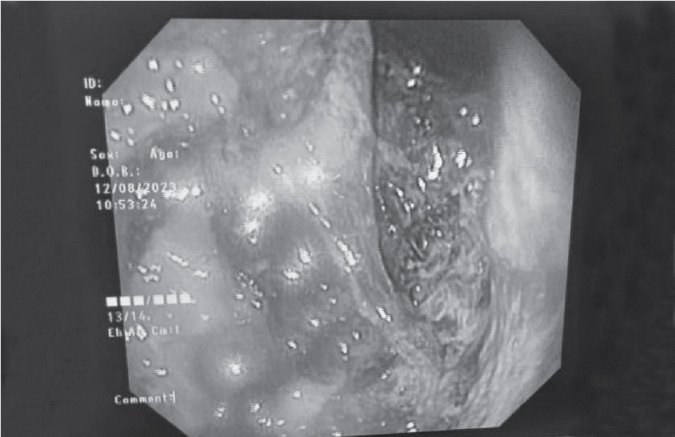

He underwent videobronchoscopy and bronchoalveolar lavage (BAL) was taken from the left lower lobe superior segment. Cartridge-based nucleic acid amplification test (CB-NAAT) done on BAL revealed high levels of M. tuberculosis with no rifampicin resistance. BAL Gram stain and ZN stain were negative.